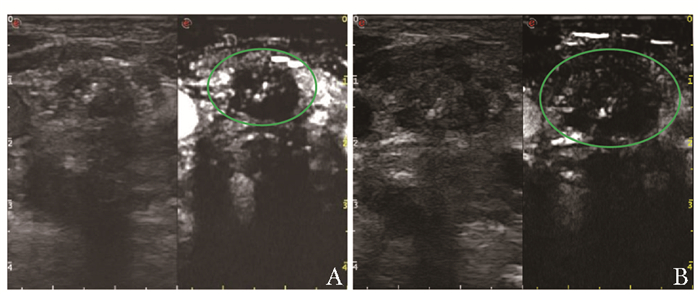

结果  共35例(46个MLNs病灶)符合纳入和排除标准的患者入选本研究。术前超声造影显示,20个MLNs为不均匀灌注(包括1个液化淋巴结),26个为均匀灌注。术后2~7 d复查超声造影显示,灌注缺损区边界较术后1 h更清晰,灌注缺损区体积比术后1 h明显增大230.40(78.03,361.17)mm3比130.62(43.06,253.66)mm3P<0.05。所有患者对PLA均耐受良好,无颈部血肿及活动性出血、感染、气管食管损伤等并发症发生。平均随访(56.7±8.9)个月,无原位淋巴结复发病例。与术前比较,末次随访时消融后病灶最大径0.00(0.00,0.00)mm比7.35(5.70,9.63)mm,P<0.05、病灶体积0.00(0.00,0.00)mm3比95.59(32.82, 169.01)mm3P<0.05均显著缩小。术后1、3个月及末次随访时消融后病灶体积缩小率分别为100(40.381,100)%、100(96.110,100)%和100(100,100)%。

Results  A total of 35 patients (46 cervical MLNs) meeting the inclusive and exclusive criteria were enrolled in this study. Preoperative CEUS showed that 20 MLNs were heterogeneously perfused (including 1 liquefied lymph node), while 26 MLNs were homogeneously perfused. During 2-7 d after PLA, CEUS showed that the boundary of the perfusion-defect area was clearer than that of 1 h after the operation, and the volume of the perfusion-defect area was significantly larger than that of 1 h after the operation230.40(78.03, 361.17)mm3 vs. 130.62(43.06, 253.66)mm3, P < 0.05. All patients tolerated well to PLA without neck hematoma, active bleeding, infection, tracheal esophageal injury, or other complications. The mean follow-up was (56.7±8.9)months, and there was no case of lymph node recurrence in situ. The maximum diameter 0.00(0.00, 0.00)mm vs. 7.35(5.70, 9.63)mm, P < 0.05 and the lesion volume 0.00(0.00, 0.00)mm3 vs. 95.59(32.82, 169.01)mm3, P < 0.05 at the last follow-up after ablation were significantly reduced compared with preoperation.